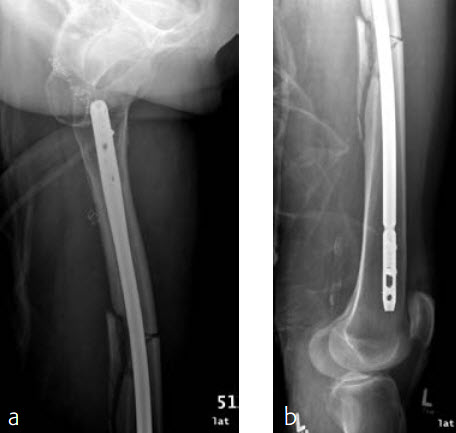

A 70-year-old female patient suffered an AO 32-B3 fracture of the left femur (Figs 3 and 4). Fixation with the FRN for a tip of the trochanter entry point (nail diameter 10 mm; nail length 400 mm; reaming to 12 mm) in standard interlocking mode (Figs 5 and 6). Proximal locking with antegrade and transverse dynamic locking positions. Distal locking with two lateral to medial locking screws in static locking position.